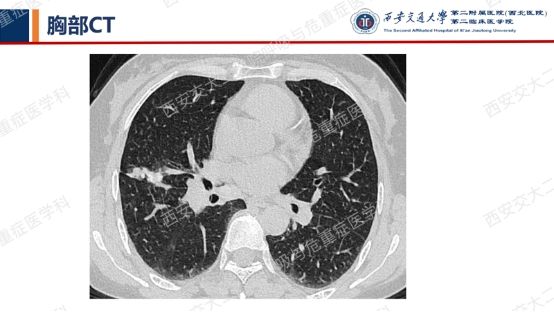

结合以上病史及胸部CT,您的初步考虑?还需要哪些检查?